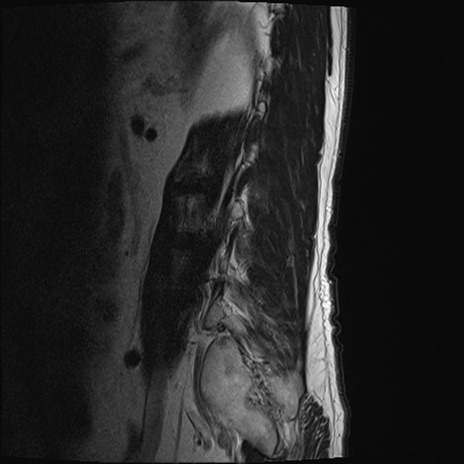

【整形】TIPS症例2 腰椎MRI T2WI(矢状断像)

【症例】70歳代男性

【主訴】左下肢痛

【現病歴】2週間前くらいから腰痛、左下肢痛あり。左臀部から大腿、下腿外側のしびれが常時ある。歩行とともに同部位の痛みあり。

【身体所見】Lasegue70-/60+、Bragard-/±、PTR ±/±、ATR -/-、IP 5/5、TA 5/4、TS 5/5、EHL 右第1足趾なし/3、FHL 5/5、hypersthesia(-)、足背動脈触知良好

異常所見と診断は?